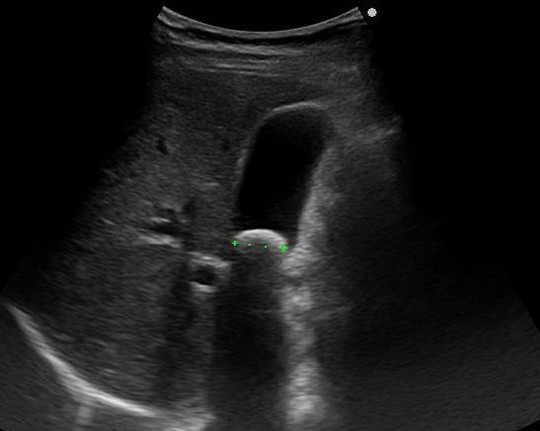

胆石症

胆石とは肝内の毛細胆管から十二指腸乳頭までの胆汁の排出経路である胆道系のどこかに結石ができる病気です。形成された結石の部位により胆嚢結石・総胆管結石・肝内結石に分けられますが、胆嚢結石が約70%と多いため、一般的に胆石というときは胆嚢結石のことを示します

無症状で健診やドックでみつかることも多い胆石症ですが、一方で食後や夜間に突発する右季肋部痛、心窩部痛、悪心・嘔吐などの症状がみられることもあります。右肩や背部に痛みが放散し胆石発作として症状が数十分~数時間持続することもあります。

腹部超音波検査やCT検査、血液検査、核磁気共鳴胆管膵管撮影や内視鏡を用いた胆管膵管造影検査で診断されます。加齢とともに増加し、中高年以上に好発します。

胆のう炎

胆嚢に生じた炎症で、90%以上は胆嚢結石により起こります。胆嚢の出口の胆嚢管に胆石が詰まり閉塞され、二次的に細菌感染が加わることで発症します。

食後の右季肋部痛や上腹部の圧痛・発熱や悪心嘔吐などがみられます。

血液検査、腹部超音波検査やCT検査で診断されます。